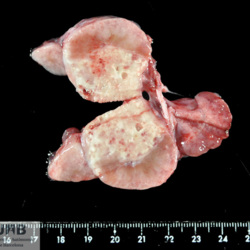

Etiquetes: SefasTB 5 total Wildlife Specie: Wildlife Organ: Lung Lesion: Pneumonia Lesion modifier: Pneumonia - Granulomatous Disease: Tuberculosis Files/Expedient: SefasTB Position: 136 (2 views) Wildlife Specie: Wildlife Organ: Lymph node Lesion: Lymphadenitis Lesion modifier: Lymphadenitis - Granulomatous Disease: Tuberculosis Files/Expedient: SefasTB Not viewed Wildlife Specie: Wildlife Organ: Lung Lesion: Pneumonia Lesion modifier: Pneumonia - Granulomatous - Multifocal Disease: Tuberculosis Files/Expedient: SefasTB Position: 252 (1 views) Wildlife Specie: Wildlife Organ: Lung Lesion: Pneumonia Lesion modifier: Pneumonia - Granulomatous - Multifocal Disease: Tuberculosis Files/Expedient: SefasTB Position: 252 (1 views) Wildlife Specie: Wildlife Organ: Lung Lesion: Pneumonia Lesion modifier: Pneumonia - Granulomatous - Multifocal Disease: Tuberculosis Files/Expedient: SefasTB Position: 252 (1 views) Títol Select...Avian (Exotic) (110)Avian (Poultry) (76)Bovine (317)Canine (935)Caprine (47)Equine (257)Feline (326)Ferret (19)General (127)Marine mammal (22)Non-human primate (20)Ovine (328)Porcine (379)Rabbit (61)Reptile (38)Rodent (28)Wildlife (91) Format Select...- (60)Abomasum (37)Adrenal gland (10)Blood (7)Blood vessel (50)Body as a whole (19)Bone (57)Bone marrow (21)Brain (93)Cloaca (1)Diaphragm (2)Ear (5)Esophagus (39)Eye (16)Fetus (12)Gallbladder (23)Gizzard (2)Heart (265)Intestine (356)Joint (32)Kidney (443)Larynx (5)Liver (326)Lung (264)Lymph node (91)Mammary gland (10)Mediastinum (1)Muscle (22)Nasal cavity (22)Nerve (7)Omasum (5)Oral cavity (63)Ovary (14)Oviduct (8)Pancreas (7)Parathyroid (5)Penis (10)Peritoneum (65)Pharynx (9)Pituitary gland (6)Placenta (7)Prostate (8)Proventriculus (3)Reticulum (1)Rumen (28)Sinus (7)Skin (181)Spinal cord (15)Spleen (105)Stomach (125)Teeth (1)Testicle (11)Thoracic cavity (31)Thymus (13)Thyroid gland (5)Tongue (32)Tonsils (11)Trachea (11)Urethra (5)Urinay bladder (61)Uterus (27)Vagina (1)Vulva (1)Yolk sac (1) Cobertura Select...- (152)Abomasitis (26)Abscess (27)Acidosis (1)Adenocarcinoma (20)Adenoma (9)Aerosacculitis (6)Agenesis (1)Agnathia (1)Alopecia (7)Amyloidosis (12)Aneurysm (6)Angiectasis (1)Anthracosis (1)Arteritis (11)Arthritis (15)Arthrogryposis (6)Artifact (4)Ascites (13)Atelectasis (8)Atherosclerosis (5)Atresia (1)Atrial septal defect (2)Atrophy (10)Autolysis (7)Bronchitis (6)Bronchopneumonia (26)Cachexia (2)Carcinoma (103)Cardiomyopathy (19)Cellulitis (2)Chemodectoma (4)Cholangiohepatitis (4)Cholangitis (19)Cholecystitis (4)Cholestasis (5)Chondrodysplasia (2)Chondrosarcoma (2)Chronic passive congestion (13)Chylothorax (2)Cirrhosis (6)Coelomitis (3)Coenurus cerebralis (4)Colitis (40)Congestion (17)Conjunctivitis (5)Coronitis (3)Cryptorchidism (3)Cyst (25)Cystitis (24)Dermatitis (69)Diaphragmatic hernia (4)Dilation (28)Discospondylitis (1)Disseminated intravascular coagulation (7)Dyschondroplasia (1)Dysplasia (29)Ectopia cordis (1)Ectopic ureter (1)Edema (55)Emphysema (5)Encephalitis (5)Endocardiosis (14)Endocarditis (26)Endometritis (5)Enteritis (118)Enterolith (6)Epulis (3)Esophagitis (14)Fasciitis (1)Fibrosis (7)Fibrous osteodystrophy (8)Fistula (1)Folliculitis (3)Fracture (2)Gastritis (34)Gingivitis (5)Glioma (8)Glomerulonephritis (21)Glossitis (25)Glycogenosis (1)Gout (8)Granuloma (2)Granulosa cell tumor (4)Hemangioma (9)Hemangiosarcoma (46)Hematoma (8)Hemoglobinuria (2)Hemopericardium (12)Hemoperitoneum (2)Hemorrhage (100)Hemosiderosis (7)Hemothorax (2)Hepatitis (78)Hernia (11)Histiocytosis (3)Hydatid cyst (11)Hydrocephalus (9)Hydrometra (1)Hydronephrosis (22)Hydropericardium (6)Hydrothorax (3)Hydroureter (5)Hyperkeratosis (8)Hyperostosis (4)Hyperplasia (37)Hypertrophy (9)Hypopigmentation (1)Hypoplasia (7)Hypopyon (1)Impaction (6)Infarction (63)Insulinoma (6)Intussusception (5)Jaundice (17)Laminitis (2)Laryngitis (2)Leiomyoma (5)Leukemia (13)Lipidosis (36)Lipoma (7)Lymphadenitis (45)Lymphadenopathy (7)Lymphangiectasia (6)Lymphangitis (5)Lymphoma (221)Malacia (11)Malignant melanoma (15)Mast cell tumor (11)Mastitis (8)Megaesophagus (2)Melanosis (3)Melena (4)Meningioma (6)Meningitis (6)Meningocele (2)Meningoencephalitis (5)Mesothelioma (5)Methemoglobinemia (2)Mineralization (10)Mucocele (5)Mucometra (1)Multilobular bone tumor (1)Mummification (3)Myelofibrosis (1)Myocarditis (4)Myositis (5)Necrosis (81)Nephritis (113)Nephroblastoma (6)Nephrosclerosis (1)Nephrosis (14)Neuritis (1)Obstruction (13)Omasitis (4)Omphalitis (1)Omphalophlebitis (7)Orchitis (4)Osteoarthrosis (5)Osteomyelitis (9)Otitis (2)Palatoschisis (3)Pancreatitis (3)Panniculitis (3)Papilloma (7)Parakeratosis (14)Patent ductus arteriosus (6)Peliosis hepatis (1)Perforation (17)Pericarditis (35)Peritonitis (39)Persistent right aortic arch (1)Pharyngitis (2)Pheochromocytoma (2)Phlebitis (2)Placentitis (6)Pleuritis (21)Pleuropneumonia (24)Pneumonia (109)Pneumothorax (3)Polycystosis (14)Polyp (5)Polyserositis (6)Posthitis (1)Proctitis (4)Prolapse (3)Prostatitis (3)Proventriculitis (1)Pyelonephritis (24)Pyometra (6)Pyothorax (4)Rhinitis (11)Rumenitis (6)Rupture (24)Salpingitis (3)Sarcoma (57)Sclerosis (1)Scoliosis (2)Seminoma (2)Sequestrum (2)Serous atrophy (14)Sinusitis (7)Splenitis (14)Splenomegaly (9)Spondylitis (6)Spondylosis (1)Stenosis (9)Stomatitis (32)Tenosynovitis (2)Teratoma (3)Thricobezoar (2)Thrombosis (16)Tonsilitis (4)Torsion (13)Tracheitis (4)Tympany (7)Typhlitis (8)Typhlocolitis (4)Ulcer (43)Urethritis (1)Urolithiasis (36)Uroperitoneum (1)Uveitis (1)Vasculitis (15)Ventricular septal defect (3)Volvulus (11) Matèria Select... - (14)- (1653)- (152)Abomasitis - Catarrhal (2)Abomasitis - Catarrhal-hemorrhagic (1)Abomasitis - Chronic (1)Abomasitis - Fibrinous-necrotizing (2)Abomasitis - Hyperplasic (5)Abomasitis - Hyperplasic - Chronic (1)Abomasitis - Necrotic (1)Abomasitis - Necrotizing (2)Abomasitis - Ulcerative (5)Adenocarcinoma (9)Aerosacculitis - Granulomatous (1)Amyloidosis - Chronic (1)Arteritis - Necrotic (2)Arteritis - Necrotizing (1)Arthritis - Chronic (4)Arthritis - Fibrinous-purulent (3)Arthritis - Serous (4)Arthritis - Subacute (1)Ascites - Serous (1)Atrophy - Serous (1)Bronchitis - Catarrhal (3)Bronchitis - Suppurative (1)Bronchopneumonia - Catarrhal-purulent (17)Bronchopneumonia - Fibrinous (1)Bronchopneumonia - Granulomatous (1)Bronchopneumonia - Purulent (1)Bronchopneumonia - Suppurative (5)Carcinoma - Adenocarcinoma (33)Carcinoma - Adenocarcinoma - Hepatocellular (2)Carcinoma - Adenocarcinoma - Mucinous (1)Carcinoma - Basosquamous (1)Carcinoma - Cholangiocellular (3)Carcinoma - Hepatocellular (4)Carcinoma - Metastatic (3)Carcinoma - Squamous cell carcinoma (13)Carcinoma - Transitional cell (2)Cardiomyopathy - Dilated (13)Cardiomyopathy - Hypertrophic (6)Cellulitis - Necrotizing (1)Cholangitis - Chronic (8)Cholangitis - Hyperplasic (3)Cholecystitis - Fibrinous-necrotizing (1)Coelomitis - Fibrinous (1)Coelomitis - Granulomatous (1)Colitis - Catarrhal (3)Colitis - Catarrhal-hemorrhagic (1)Colitis - Fibrinous (1)Colitis - Fibrinous-necrotizing (1)Colitis - Fibrinous-necrotizing (Diphtheritic) (6)Colitis - Granulomatous (2)Colitis - Hemorrhagic (4)Colitis - Hemorrhagic-necrotizing (3)Colitis - Necrotizing (2)Colitis - Ulcerative (6)Congestion - Chronic (2)Conjunctivitis - Hyperplasic (1)Conjunctivitis - Purulent (3)Coronitis - Ulcerative (1)Cystitis - Chronic (3)Cystitis - Fibrinous (1)Cystitis - Fibrinous-necrotizing (1)Cystitis - Follicular (1)Cystitis - Hemorrhagic (6)Cystitis - Hemorrhagic-ulcerative (1)Cystitis - Necrotizing (9)Cystitis - Perforated (1)Dermatitis - Granulomatous (14)Dermatitis - Hyperkeratotic (10)Dermatitis - Hyperplasic (proliferative) (1)Dermatitis - Hyperplastic (10)Dermatitis - Necrotizing (4)Dermatitis - Pustular (4)Dermatitis - Ulcerative (2)Dilation - Chronic (1)Discospondylitis - Necrotizing (1)Dysplasia - Follicular (5)Edema - Interstitial (6)Emphysema - Interstitial (1)Encephalitis - Granulomatous (1)Encephalitis - Nonsuppurative (1)Endocardiosis - Mitral (7)Endocardiosis - Mitral - Chronic (5)Endocarditis - Valvular (6)Endocarditis - Valvular - Mitral (7)Endocarditis - Valvular - Pulmonic (1)Endocarditis - Valvular - Subacute (1)Endocarditis - Valvular - Subaortic (5)Endocarditis - Valvular - Tricuspid (4)Endometritis - Purulent (3)Endometritis - Purulent-hemorrhagic (2)Enteritis - Catarrhal (23)Enteritis - Catarrhal - Acute (1)Enteritis - Catarrhal-hemorrhagic (5)Enteritis - Catarrhal-hemorrhagic - Acute (2)Enteritis - Fibrinous (16)Enteritis - Fibrinous - Acute (3)Enteritis - Fibrinous-necrotizing (7)Enteritis - Granulomatous (14)Enteritis - Granulomatous - Chronic (1)Enteritis - Granulomatous - Multifocal (1)Enteritis - Hemorrhagic (17)Enteritis - Hemorrhagic - Acute (1)Enteritis - Hemorrhagic-necrotizing (1)Enteritis - Hyperplasic (proliferative) (4)Enteritis - Necrotizing (4)Enteritis - Necrotizing - Acute (1)Enteritis - Necrotizing - Hemorrhagic (1)Enteritis - Necrotizing-ulcerative (2)Enteritis - Ulcerative (1)Enteritis - Ulcerative-hemorrhagic (1)Esophagitis - Erosive-ulcerative (6)Esophagitis - Necrotizing (4)Esophagitis - Ulcerative (1)Esophagitis - Ulcerative-necrotizing (1)Fasciitis - Fibrinous-purulent (1)Folliculitis - Purulent (2)Gastritis - Catarrhal (2)Gastritis - Chronic (1)Gastritis - Follicular (1)Gastritis - Hemorrhagic (2)Gastritis - Hemorrhagic-necrotizing (1)Gastritis - Hypertrophic (2)Gastritis - Inclusion bodies (1)Gastritis - Mineralization (1)Gastritis - Mycotic (1)Gastritis - Necrotizing (2)Gastritis - Ulcerative (6)Gastritis - Uremic (3)Gingivitis - Erosive (2)Gingivitis - Hyperplasic (proliferative) (1)Gingivitis - Necrotizing (1)Glomerulonephritis - Chronic (7)Glomerulonephritis - Membranoproliferative (3)Glomerulonephritis - Membranoproliferative - Chronic (1)Glomerulonephritis - Membranous (3)Glomerulonephritis - Membranous - Chronic (1)Glomerulonephritis - Proliferative (2)Glomerulonephritis - Subacute (1)Glossitis - Erosive (2)Glossitis - Granulomatous (6)Glossitis - Hyperplasic (1)Glossitis - Hyperplasic (proliferative) (2)Glossitis - Hyperplastic (1)Glossitis - Necrotizing (2)Glossitis - Necrotizing - Focal (1)Glossitis - Ulcerative (6)Glossitis - Ulcerative - Multifocal (1)Glossitis - Ulcerative - Subacute (1)Glycogenosis (1)Granuloma - Eosinophilic (1)Hemangiosarcoma - Metastatic (2)Hemorrhage - Acute (1)Hemorrhage - Subcapsular (3)Hepatitis - Abscess (9)Hepatitis - Acute (3)Hepatitis - Chronic (4)Hepatitis - Chronic interstitial (6)Hepatitis - Granulomatous (7)Hepatitis - Interstitial - Multifocal (1)Hepatitis - Interstitial - Subacute (1)Hepatitis - Necrotizing (17)Hepatitis - Necrotizing - Acute (2)Hepatitis - Necrotizing - Hemorrhagic (1)Hepatitis - Necrotizing - Subacute (1)Hepatitis - Pyogranulomatous (7)Hepatitis - Subacute (4)Hydronephrosis - Chronic (1)Hydropericardium - Chronic (1)Hyperplasia - Erythroid (1)Hyperplasia - Lymphoid (3)Hyperplasia - Myeloid (1)Hyperplasia - Nodular (8)Hypertrophy - Concentric (2)Hypertrophy - Eccentric (3)Infarction - Acute (17)Infarction - Acute - Multifocal (2)Infarction - Chronic (5)Infarction - Chronic - Multifocal (1)Infarction - Subacute (18)Infarction - Subacute - Focal (2)Laminitis - Chronic (2)Laryngitis - Necrotic (1)Laryngitis - Necrotizing (1)Leukemia - Lymphoid leukemia (2)Leukemia - Non-lymphoid leukemia (6)Lipidosis - Multifocal (1)Lipidosis - Panlobular (1)Lipidosis - Panlobular - Generalized (2)Lymphadenitis - Granulomatous (24)Lymphadenitis - Granulomatous - Chronic (3)Lymphadenitis - Hemorrhagic (1)Lymphadenitis - Necrotizing (5)Lymphadenitis - Necrotizing (caseous) (11)Lymphangitis - Granulomatous (1)Lymphangitis - Purulent (1)Lymphangitis - Ulcerative (1)Lymphoma - Alimentary lymphoma (7)Lymphoma - Cutaneous lymphoma (6)Lymphoma - Lymphosarcoma (2)Lymphoma - Mediastinal lymphoma (1)Lymphoma - Multicentric lymphoma (29)Malignant melanoma - Malignant (1)Malignant melanoma - Metastatic (1)Mast cell tumor - Metastatic (1)Mastitis - Fibrinous-purulent (2)Mastitis - Necrotic (1)Mastitis - Purulent (3)Mastitis - Suppurative (1)Meningitis - Fibrinous-purulent (2)Meningitis - Purulent (4)Meningoencephalitis - Necrotizing (3)Meningoencephalitis - Nonsuppurative (2)Mineralization - Metastatic (4)Myocarditis - Fibrous - Chronic (1)Myocarditis - Granulomatous (1)Myositis - Purulent (2)Necrosis - Acute (1)Necrosis - Cortical (5)Necrosis - Follicular (1)Necrosis - Papillary (8)Necrosis - Papillary - Acute (3)Necrosis - Subacute (3)Necrosis - Tubular (6)Nephritis - Embolic (2)Nephritis - Embolic suppurative (7)Nephritis - Granulomatous (27)Nephritis - Granulomatous - Chronic (1)Nephritis - Granulomatous - Multifocal (1)Nephritis - Interstitial (6)Nephritis - Interstitial - Acute (4)Nephritis - Interstitial - Chronic (41)Nephritis - Interstitial - Subacute (12)Nephritis - Purulent (7)Nephritis - Purulent - Acute (2)Nephritis - Purulent - Multifocal (3)Nephrosis - Cholemic (3)Nephrosis - Hemoglobinuric (10)Omasitis - Fibrinous-necrotizing (1)Omasitis - Hyperkeratotic (1)Omasitis - Necrotizing (2)Omphalophlebitis - Fibrinous-purulent (2)Omphalophlebitis - Purulent (3)Orchitis - Necrotizing (1)Osteomyelitis - Necrotizing (7)Osteomyelitis - Purulent (2)Otitis - Necrotizing (1)Otitis - Proliferative (1)Pancreatitis - Acute (1)Pancreatitis - Chronic (1)Pancreatitis - Granulomatous (1)Panniculitis - Fibrinous-purulent (1)Panniculitis - Necrotic (1)Panniculitis - Parasitic (1)Perforation - Acute (2)Pericarditis - Fibrinous (19)Pericarditis - Fibrinous - Subacute (1)Pericarditis - Fibrinous-necrotizing (1)Pericarditis - Fibrinous-purulent (3)Pericarditis - Fibrous (1)Pericarditis - Fibrous - Chronic (1)Pericarditis - Gangrenous (6)Pericarditis - Granulomatous (1)Pericarditis - Granulomatous - Chronic (2)Peritonitis - Acute (1)Peritonitis - Fibrinous (11)Peritonitis - Fibrinous - Subacute (1)Peritonitis - Fibrinous-purulent (5)Peritonitis - Fibrous (3)Peritonitis - Granulomatous (6)Peritonitis - Purulent (1)Peritonitis - Purulent-hemorrhagic (1)Peritonitis - Pyogranulomatous (3)Pharyngitis - Fibrinous-necrotizing (1)Pharyngitis - Ulcerative (1)Pheochromocytoma - Metastatic (1)Phlebitis - Purulent (1)Placentitis - Fibrinous-necrotizing (1)Placentitis - Necrotic (1)Placentitis - Necrotizing (1)Pleuritis - Chronic (1)Pleuritis - Fibrinous (3)Pleuritis - Fibrinous-purulent (2)Pleuritis - Fibrous (2)Pleuritis - Granulomatous (3)Pleuritis - Hyperplastic (2)Pleuritis - Purulent (2)Pleuritis - Pyogranulomatous (1)Pleuropneumonia - Fibrinous (13)Pleuropneumonia - Fibrinous-necrotizing (5)Pleuropneumonia - Granulomatous (2)Pleuropneumonia - Hemorrhagic-necrotizing (4)Pneumonia - Aspiration (11)Pneumonia - Bronchointerstitial (4)Pneumonia - Bronchointerstitial - Subacute (1)Pneumonia - Embolic (5)Pneumonia - Granulomatous (37)Pneumonia - Granulomatous - Multifocal (4)Pneumonia - Hemorrhagic-necrotizing (2)Pneumonia - Interstitial (7)Pneumonia - Interstitial - Acute (8)Pneumonia - Interstitial - Chronic (6)Pneumonia - Interstitial - Subacute (15)Pneumonia - Necrotizing (2)Pneumonia - Pyogranulomatous (2)Pneumonia - Verminous (5)Polyserositis - Fibrinous (6)Polyserositis - Fibrous (1)Proctitis - Fibrinous-necrotizing (1)Proctitis - Parasitic (2)Prostatitis - Purulent (1)Pyelonephritis - Acute (2)Pyelonephritis - Chronic (3)Rhinitis - Catarrhal (2)Rhinitis - Fibrinous (1)Rhinitis - Granulomatous (4)Rhinitis - Purulent (3)Rumenitis - Acute (1)Rumenitis - Erosive (1)Rumenitis - Necrotizing (1)Rupture - Acute (3)Sarcoma - Fibrosarcoma (12)Sarcoma - Hemangiosarcoma (11)Sarcoma - Histiocytic (7)Sarcoma - Metastatic (1)Sarcoma - Multilobular tumor of bone (1)Sequestrum - Chronic (2)Sinusitis - Suppurative (1)Splenitis - Granulomatous (8)Splenitis - Granulomatous - Chronic (1)Splenitis - Necrotizing (3)Splenitis - Necrotizing (caseous) (2)Spondylitis - Necrotizing (2)Stenosis - Intestinal (1)Stenosis - Valvular - Subaortic (4)Stomatitis - Erosive (12)Stomatitis - Erosive-ulcerative (3)Stomatitis - Fibrinous-necrotizing (1)Stomatitis - Fibrinous-necrotizing (Diphtheritic) (1)Stomatitis - Granulomatous (1)Stomatitis - Hyperplasic (1)Stomatitis - Hyperplasic (proliferative) (1)Stomatitis - Necrotizing (2)Stomatitis - Ulcerative (5)Stomatitis - Ulcerative - Multifocal (1)Stomatitis - Ulcerative-necrotizing (1)Tonsilitis - Necrotizing (4)Torsion - Acute passive hyperemia (5)Tracheitis - Catarrhal (3)Tracheitis - Fibrinous (1)Tracheitis - Granulomatous (1)Typhlitis - Catarrhal (1)Typhlitis - Fibrinous-necrotizing (2)Typhlitis - Hemorrhagic (2)Typhlitis - Ulcerative-hemorrhagic (1)Typhlocolitis - Fibrinous-necrotizing (2)Typhlocolitis - Proliferative (1)Ulcer - Chronic (6)Ulcer - Multifocal (2)Ulcer - Mycotic (1)Ulcer - Perforated (6)Urethritis - Hemorrhagic (1)Urolithiasis - Chronic (2)Uveitis - Granulomatous (1)Vasculitis - Granulomatous (1)Vasculitis - Necrotizing (1) Editor Select...- (1970)Acidosis (2)Actinobacillosis (Pleuropneumonia) (11)Aelurostrongylosis (2)African horse sickness (13)African swine fever (14)Alopecia X (1)Anaplasmosis (4)Anthrax (2)Aortic thromboembolism (feline) (7)Ascariasis (15)Aspergillosis (18)Atopic dermatitis (1)Atrophic rhinitis (3)Babesiosis (6)Blackhead (1)Bluetongue (11)Border disease (2)Bovine viral diarrhea (21)Brucellosis (2)Candidiasis (5)Canine distemper (14)Caprine arthritis-encephalitis (2)Capture myopathy (1)Cardiac insufficiency (17)Caseous lymphadenitis (7)Chlamydiosis (2)Classical swine fever (19)Clostridiosis (19)Coccidiosis (9)Coenurosis (4)Colibacillosis (21)Contagious ecthyma (7)Copper toxicosis (11)Cowdriosis (Heartwater) (3)Cryptococcosis (3)Cryptosporidiosis (2)Cysticercosis (23)Demodicosis (1)Diabetes (1)Dicrocoeliosis (5)Dictyocaulosis (4)Dirofilariasis (7)Discoid lupus erythematosus (3)Echinococcosis (17)Edema disease (7)Egg drop syndrome (1)Encephalitozoonosis (5)Enterotoxemia (1)Enzootic bovine leukosis (46)Epitheliogenesis imperfecta (3)Equine rhinopneumonitis (2)Equine verminous arteritis (strongylosis) (7)Erysipelas (5)Exudative epidermitis (7)Fasciolasis (11)Feline eosinophilic dermatoses (1)Feline hepatic lipidosis (8)Feline histiocytosis (4)Feline infectious peritonitis (38)Feline leukemia (4)Feline lower urinary tract disease (3)Feline panleukopenia (16)Feline viral rhinotracheitis (1)Flea allergy dermatitis (1)Foot and mouth disease (2)Gasterophilosis (4)Glasser's disease (15)Gousiekte (4)Gout (6)Haemonchosis (9)Hemolytic anemia (4)Hemorrhagic diathesis (1)Hepatic insufficiency (11)Hepatosis dietetica (7)Herpesvirosis (6)Hyperadrenocorticism (7)Hyperparathyroidism (10)Hypertrophic osteopathy (6)Hypervitaminosis D (1)Hypodermosis (1)Inclusion body hepatitis (4)Infectious bovine rhinotracheitis (5)Infectious bronchitis (5)Infectious canine hepatitis (13)Influenza (4)Juvenile nephropathy (8)Lamb dysentery (4)Leishmaniasis (28)Leptospirosis (1)Leukosis (5)Listeriosis (4)Lumpy skin disease (3)Maedi-visna (4)Malignant catarrhal fever (12)Mange (6)Mannheimiosis (5)Marek's disease (7)Metabolic bone disease (2)Mucoid enteropathy (5)Mulberry heart disease (5)Myasis (1)Mycobacteriosis (22)Mycosis fungoides (6)Myxomatosis (3)Necrobacillosis (5)Neonatal isoerythrolysis (6)Nocardiosis (4)Oestrosis (2)Onchocerciasis (1)Osteochondrosis (1)Ostertagiosis (6)Ovine pulmonary adenocarcinoma (5)Oxyuriasis (1)Pacheco's disease (4)Papillomatosis (6)Paratuberculosis (18)Parvovirosis (17)Pasteurellosis (11)Pemphigus foliaceus (1)Periodontal disease (1)Polioencephalomalacia of ruminants (4)Polyarteritis nodosa (3)Polycystic kidney disease (13)Porcine circovirosis (11)Porcine dermatitis and nephropathy syndrome (9)Porcine proliferative enteropathy (4)Porcine reproductive and respiratory syndrome (6)Porcine stress syndrome (1)Pox (13)Pregnancy toxemia (3)Proventricular dilatation disease (2)Pseudotuberculosis (yersiniosis) (2)Psittacine beak and feather disease (PBFD) (5)Pyoderma (4)Q fever (4)Rabbit hemorrhagic disease (2)Renal insufficiency (12)Reticuloendotheliosis (2)Rhodococcosis (1)Rickets (1)Rinderpest (2)Salmonellosis (34)Sarcosporidiosis (2)Schmallenberg (7)Septicemia (23)Spirocercosis (11)Streptococcosis (5)Strongylosis (1)Swine dysentery (5)Systemic coronavirosis (5)Tetralogy of Fallot (5)Theileriosis (13)Thromboembolism (5)Toxoplasmosis (11)Transmissible viral proventriculitis (1)Traumatic reticuloperitonitis (3)Traumatism (16)Tuberculosis (58)Ulcerative lymphangitis (1)Uremic syndrome (20)Viral arthritis (6)White muscle disease (9)Wobbler syndrome (2)Xanthomatosis (1)Zygomycosis (4) Idioma Select...- (1180)Bacterial (501)Degeneration (106)Fungal (46)Hemodynamic (112)Idiopathic (22)Inflammation (58)Malformation (88)Neoplasia (343)Nutritional (41)Parasitic (243)Physical/Chemical (93)Toxic (44)Viral (304) Ítem destacat Canine Intervertebral disk herniation in T6-T7 and T7-T8 with medullary compression. There is also ventral protrusion with spondylosis. Other intervertebral…